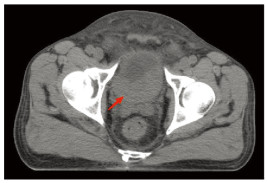

入院后进行相关的实验室检查,血常规提示血红蛋白为82 g/L。肝功能、肾功能、电解质、凝血相关指标、CEA、CA19-9、细胞角蛋白正常。下腹部CT扫描显示膀胱后壁弥漫性增厚,周围组织边界不清,见图 1。CT扫描还显示左侧输尿管积液,左侧肾盂扩张和左侧肾周积液,未发现明显的淋巴结肿大或远处转移。膀胱镜活检病理提示:(膀胱)高级别浸润性浆细胞样尿路上皮癌,HE染色见图 2。免疫组织化学:CK(+),P40(+),P63(+),CK高(+),CK7(+),CK8/18(+),CK20(+),CD138(+),CD38(-),CD56(-),CK5/6(-),EMA(-),Desmin(-),Vimentin(-),Syn(-),CgA(-),LCA(-),MUM-1(-),Ki-67(+,约80%)。